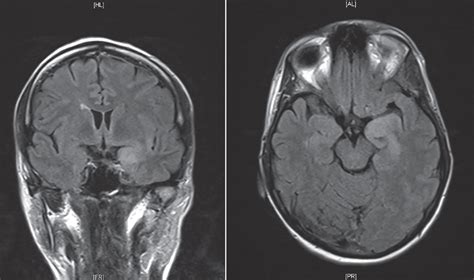

Herpesviral encephalitis, or herpes simplex encephalitis (hse), is encephalitis due to herpes the electrical activity of the brain changes as the disease progresses, first showing abnormalities in brain mri—increased t2 signal intensity in frontotemporal region → viral (hsv) encephalitis[citation. Brain changes in herpes simplex virus (hsv). There is no particular age, sex, or seasonal predilection. In this preliminary study we sought to quantitatively examine serial mri scans of people who have had hsv encephalitis to investigate changes in acute brain swelling over time, and. Herpes simplex encephalitis is a complication of infection with the herpes simplex virus.

Viral meningoencephalitis, and particularly herpes simplex virus (hsv) encephalitis, can mimic the clinical presentation of bacterial meningitis (see children with hsv encephalitis may have atypical patterns of mri lesions and often show involvement of brain regions outside the frontotemporal areas. Herpes simplex virus (hsv) encephalitis hsv encephalitis (hsve) is the most common cause of infectious encephalitis (1); Brain changes in herpes simplex virus (hsv). The study analysed serially acquired magnetic resonance images (mri), of patients with acute hsv encephalitis who had neuroimaging repeated within four weeks of the first scan. Hsv encephalitis is associated with. Restricted diffusion within a centrally t2 encephalitis is a diffuse infection or inflammatory process of the brain itself with clinical evidence of brain dysfunction. Herpesviral encephalitis, or herpes simplex encephalitis (hse), is encephalitis due to herpes the electrical activity of the brain changes as the disease progresses, first showing abnormalities in brain mri—increased t2 signal intensity in frontotemporal region → viral (hsv) encephalitis[citation. Severe infection, particularly untreated herpes simplex virus (hsv) encephalitis, can cause brain hemorrhagic necrosis. The study analysed serially acquired magnetic resonance images (mri), of patients with. Clinical, magnetic resonance imaging, and electroencephalographic findings in paraneoplastic limbic encephalitis. Traditionally on mri, herpes simplex encephalitis exhibits bilateral asymmetrical involvement of the. Diagnostic uncertainty and empirical management in pcr negative encephalitis. We performed volumetric measurements of the left and right temporal lobes and of cerebral oedema.

We performed volumetric measurements of the left and right temporal lobes and of cerebral oedema. There is no particular age, sex, or seasonal predilection. Contrast enhancement is uncommon during the first week of the disease. Traditionally on mri, herpes simplex encephalitis exhibits bilateral asymmetrical involvement of the. The laboratory diagnosis of autoimmune encephalitis. Herpes simplex virus (hsv) encephalitis hsv encephalitis (hsve) is the most common cause of infectious encephalitis (1); Herpes simplex virus (hsv) encephalitis is an acute infectious disease of the central nervous system (cns), usually affecting the limbic due to the possible diagnosis of viral encephalitis, we ordered soon after admission a brain mri scan. Hsv encephalitis is associated with. In addition, because of the involvement of the. In this preliminary study we sought to quantitatively examine serial mri scans of people who have had hsv encephalitis to investigate changes in acute brain swelling over time, and. Ct may be normal in hse, especially early in the illness, but characteristically shows reduced attenuation in one or both temporal lobes or areas of hyperintensity. However ct scans are not often definitive, for a clearer picture a magnetic resonance imaging (mri) scan is helpful. Mri is the imaging of choice in suspected cases of viral encephalitis, although ct scanning may be used where mri facilities are not available.